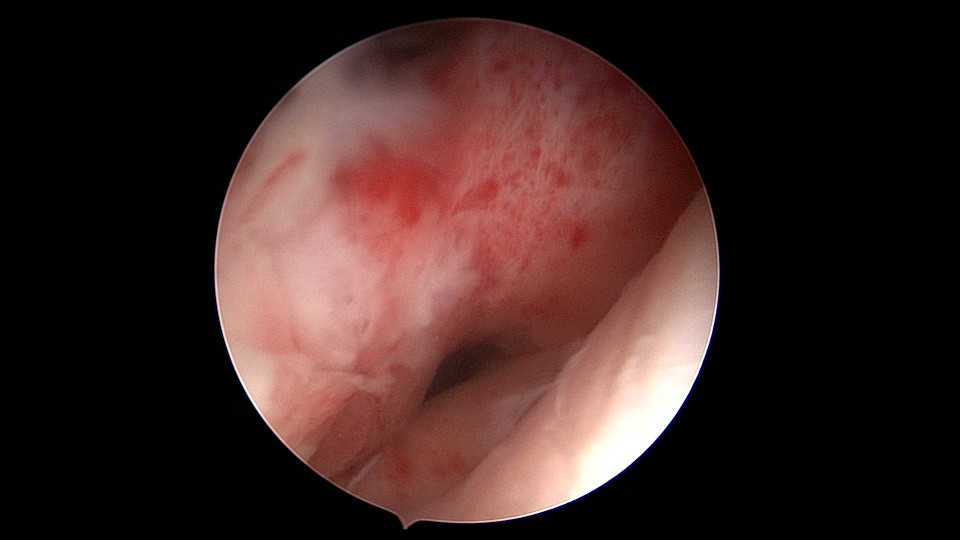

患者53岁,G3P1,剖宫产1次。安环13年,绝经8年,外院取环失败。患者阴道、宫颈及子宫萎缩,很难置入扩阴器,很难牵拉宫颈,宫颈外口位于前穹隆顶端,子宫极度前倾前屈位,且子宫与盆壁粘连,被拉长,宫腔镜很难进入,B超监护下异物钳扩张宫颈管上段及宫颈内口,宫腔镜艰难进入宫腔,见T型环两横臂嵌顿于两侧宫角,尾丝断裂,异物钳取出节育环,宫腔未见其他异常。